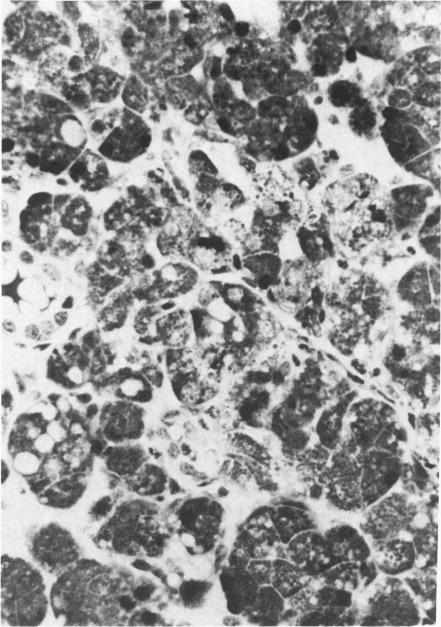

Acute and chronic salivary gland dysfunction are common sequelae of radiotherapy for head and neck cancer; but the associated morphologic changes, especially of the acute damage, have received relatively little study. For investigation of the morphologic characteristics of acute radiation injury to parotid glands, rhesus monkeys were studied 1-72 hours after parotid irradiation with single doses of 2.5-15.0 Gy. The acute damage from all doses was clearly expressed by 24 hours. Histologically, parotid glands irradiated with 2.5 or 5.0 Gy had random degeneration and necrosis of the serous acinar cells. Doses of 7.5-15.0 Gy produced widespread degeneration along with necrosis of whole acini. Serous cell damage was accompanied by neutrophilic inflammation that subsided after 24 hours to become replaced by plasma cell and lymphocytic infiltrates. Parotid glands receiving 7.5-15.0 Gy were atrophic at 16-22 weeks after irradiation and showed no recovery by 40 weeks. Although parotid acinar cells are well-differentiated nondividing cells, these observations show that they express lethal radiation injury in interphase within hours of receiving a radiation dose as low as 2.5 Gy. This is unlike most mammalian cells that express radiation injury during mitosis. Chronic atrophy is a consequence of this direct, irreversible, and early injury, rather than the result of radiation-induced changes in the vasculature.

急性和慢性唾液腺功能障碍是头颈癌放疗常见的后遗症;但相关的形态学变化,尤其是急性损伤的变化,研究相对较少。为了研究腮腺急性放射性损伤的形态学特征,对恒河猴单次腮腺照射2.5 - 15.0 Gy后1 - 72小时进行了研究。所有剂量的急性损伤在24小时时均明显表现出来。组织学上,接受2.5或5.0 Gy照射的腮腺浆液性腺泡细胞出现随机变性和坏死。7.5 - 15.0 Gy的剂量导致广泛变性以及整个腺泡坏死。浆液细胞损伤伴有中性粒细胞炎症,24小时后消退,继而被浆细胞和淋巴细胞浸润取代。接受7.5 - 15.0 Gy照射的腮腺在照射后16 - 22周出现萎缩,至40周仍未恢复。尽管腮腺腺泡细胞是分化良好的非分裂细胞,但这些观察结果表明,它们在接受低至2.5 Gy的辐射剂量后数小时内的间期就表现出致死性辐射损伤。这与大多数在有丝分裂期间表现出辐射损伤的哺乳动物细胞不同。慢性萎缩是这种直接、不可逆和早期损伤的结果,而非辐射诱导血管变化的结果。